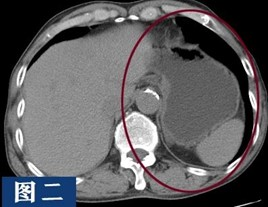

以上为同一个患者两次检查的结果,第一次没有喝水,胃没有充盈;第二次是喝水后,胃已充盈。大家可以很清楚的看到,没有充盈的胃腔且有食物残留,好似长了肿块一样,会干扰影像医生的诊断。

通过这个病例展示,患者做腹部CT检查前空腹及喝足量水是很有必要的。因腹腔内脏器较多,且大多数属于消化系统,有空腔脏器(胃、肠道、膀胱等),也有实质脏器(肝、胰腺、脾脏、肾脏等),由于缺乏天然对比,腹腔内的结构往往不能被清楚的分辨,水作为一种天然对比剂,可以增强组织与周围结构的对比度。通过喝水,胃肠道可以充分膨胀,使其内部结构更加清晰;此外,喝水还有助于减少胃肠道中气体的对图像的干扰,可以更好的帮助影像医生观察胃肠道的形态,有无异物或肿瘤等情况,减少误诊或漏诊的发生。